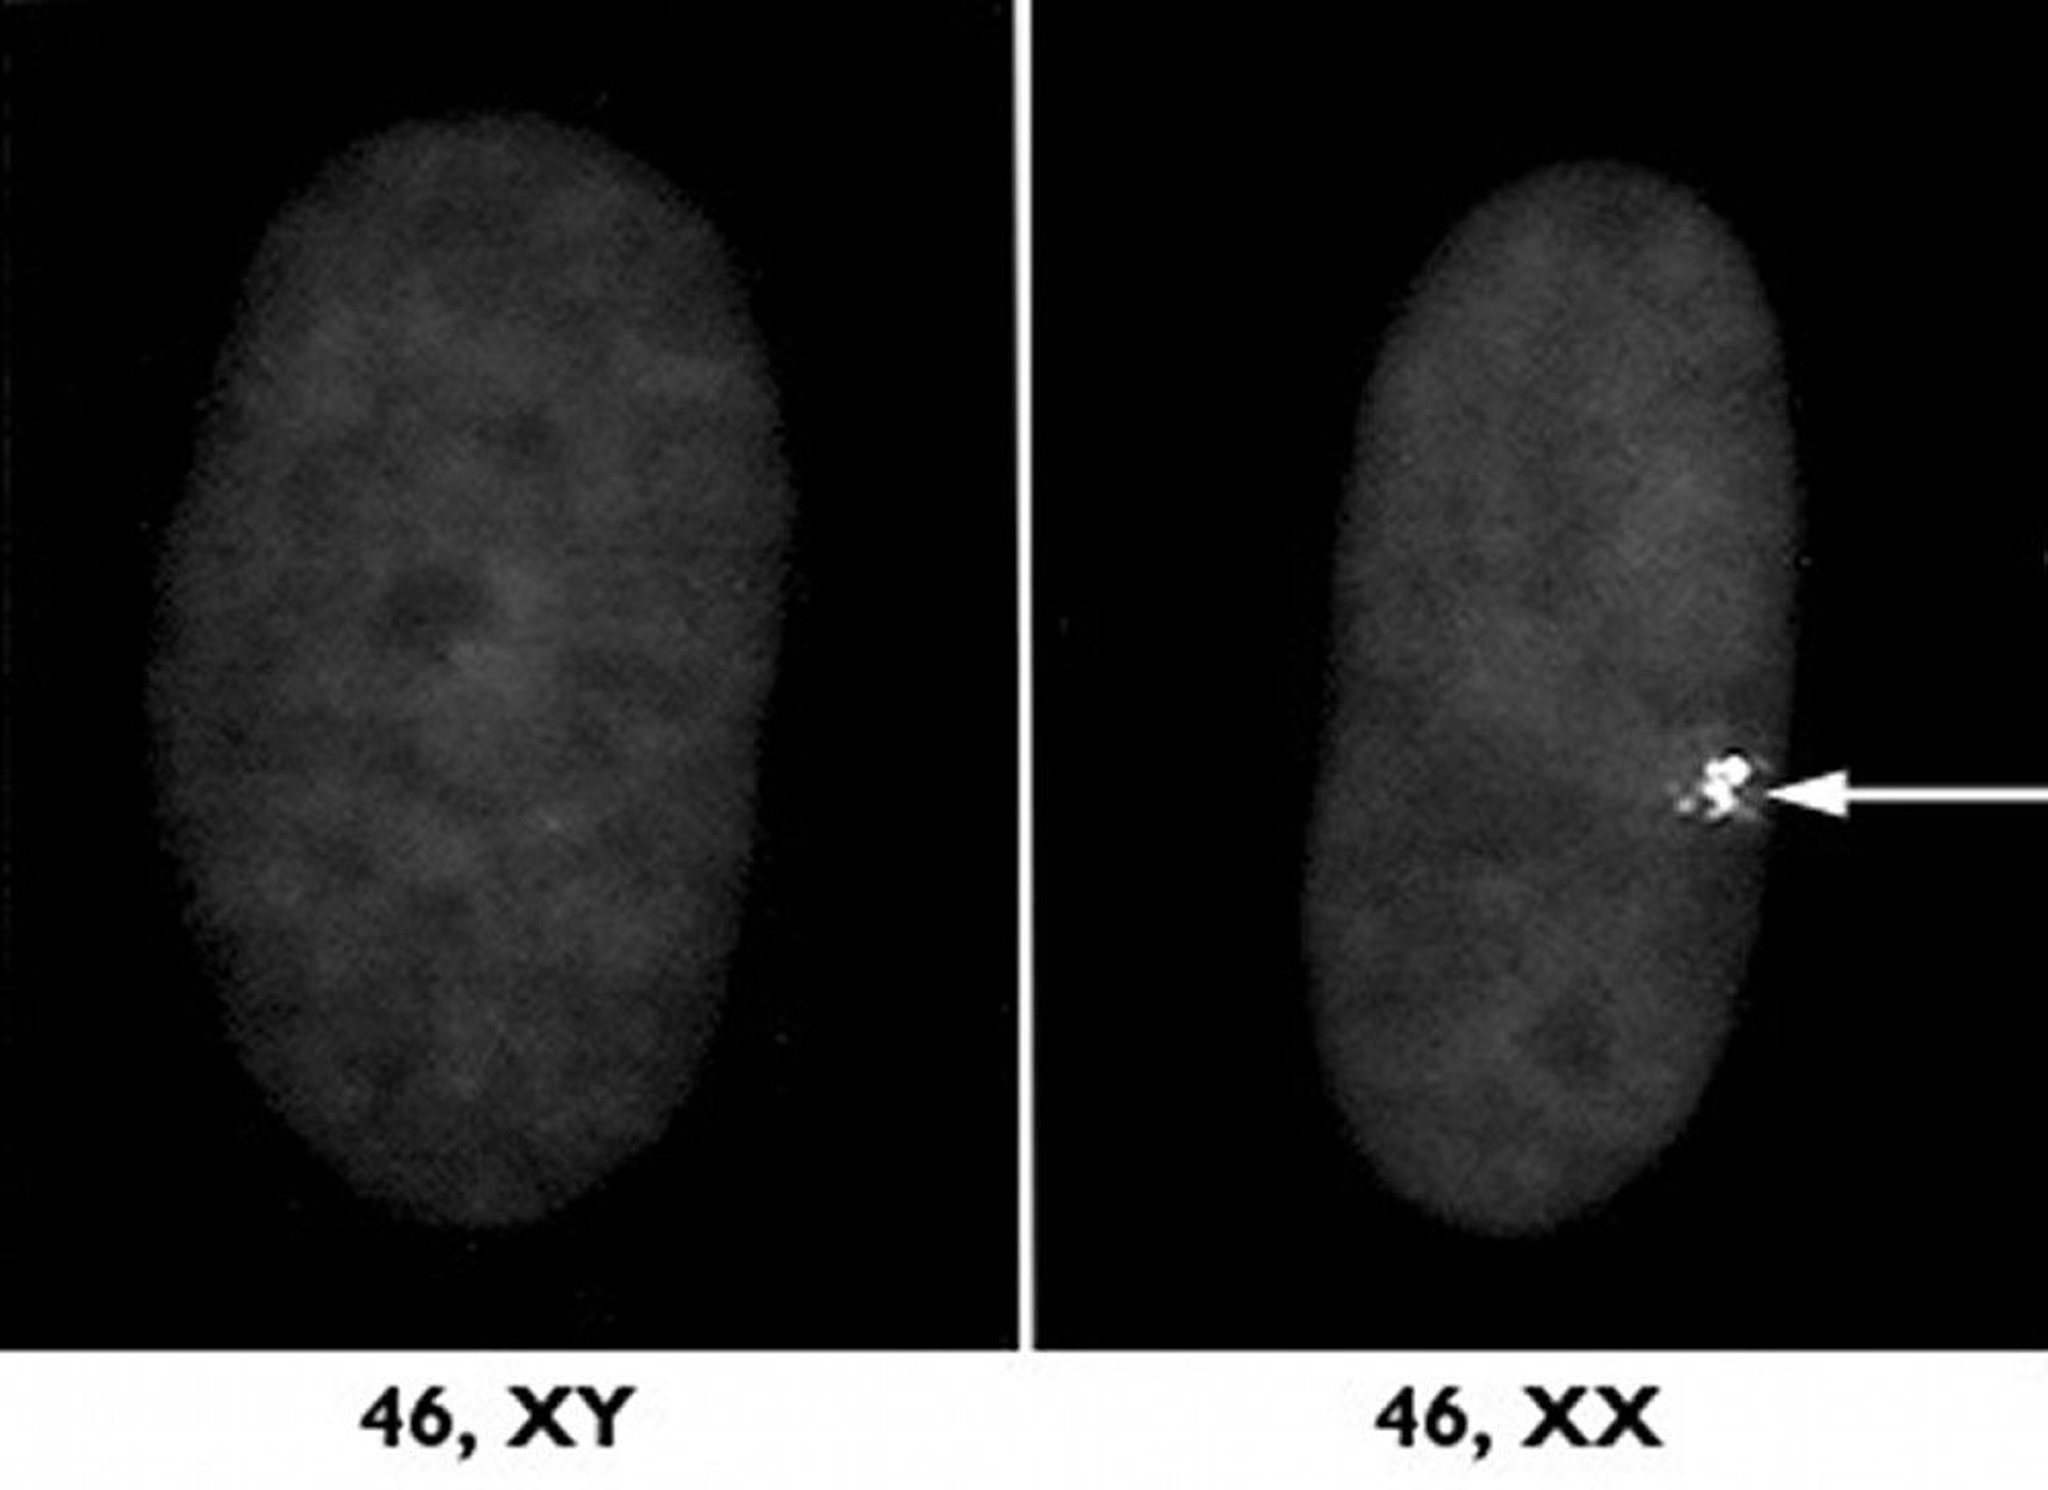

Kromosom seks

Sepasang kromosom seks menentukan apakah janin akan berjenis kelamin laki-laki atau perempuan. Laki-laki memiliki satu kromosom X dan satu kromosom Y. X pada laki-laki berasal dari ibunya dan Y berasal dari ayahnya. Perempuan memiliki dua kromosom X, satu dari ibu dan satu dari ayah. Dengan cara tertentu, kromosom seks memiliki fungsi berbeda dibandingkan kromosom nonseks.

Kromosom Y yang lebih kecil membawa gen yang menentukan jenis kelamin laki-laki serta beberapa gen lainnya. Kromosom X mengandung lebih banyak gen daripada kromosom Y, banyak di antaranya memiliki fungsi selain menentukan jenis kelamin dan tidak memiliki padanan pada kromosom Y. Pada laki-laki, karena tidak ada kromosom X kedua, maka gen ekstra pada kromosom X ini tidak dipasangkan dan hampir semuanya diekspresikan. Gen pada kromosom X disebut sebagai gen terpaut seks, atau terpaut X.

Biasanya, pada kromosom nonseks, gen pada kedua pasangan kromosom mampu diekspresikan sepenuhnya. Namun, pada wanita, sebagian besar gen pada salah satu dari dua kromosom X dimatikan melalui proses yang disebut inaktivasi X (kecuali dalam sel telur di ovarium). Inaktivasi X terjadi di awal kehidupan janin. Dalam beberapa sel, X dari ayah menjadi tidak aktif, dan dalam sel lain, X dari ibu menjadi tidak aktif. Dengan demikian, satu sel dapat mengekspresikan gen dari ibu orang tersebut dan sel lainnya mengekspresikan gen dari ayah orang tersebut. Karena inaktivasi X, tidak adanya satu kromosom X biasanya menyebabkan abnormalitas yang relatif kecil (seperti sindrom Turner). Dengan demikian, hilangnya kromosom X jauh lebih tidak berbahaya dibandingkan hilangnya kromosom nonseks (lihat Gambaran Umum Abnormalitas Kromosom Seks).